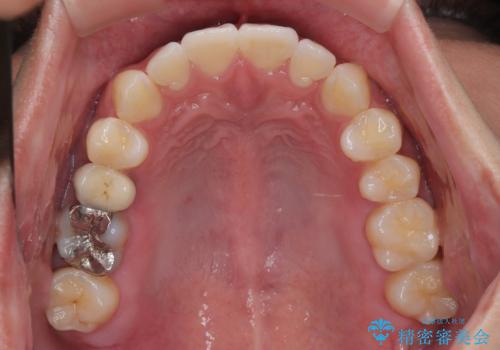

- 前歯の反対咬合などを気にして来院された患者様です。

ワイヤー矯正、マウスピース矯正どちらでも対応可能であったので、ご本人の希望によりインビザラインにて矯正治療を行うこととしました。

毎日の装着時間をしっかりと守ってくださり、1年強の短期間で、あっという間に治療を終えることができました。